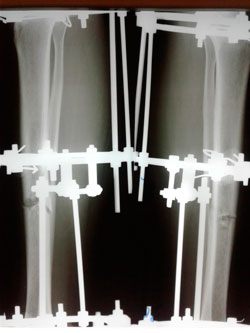

в процессе

Вложения

image-25-08-20-12-19-1.jpg